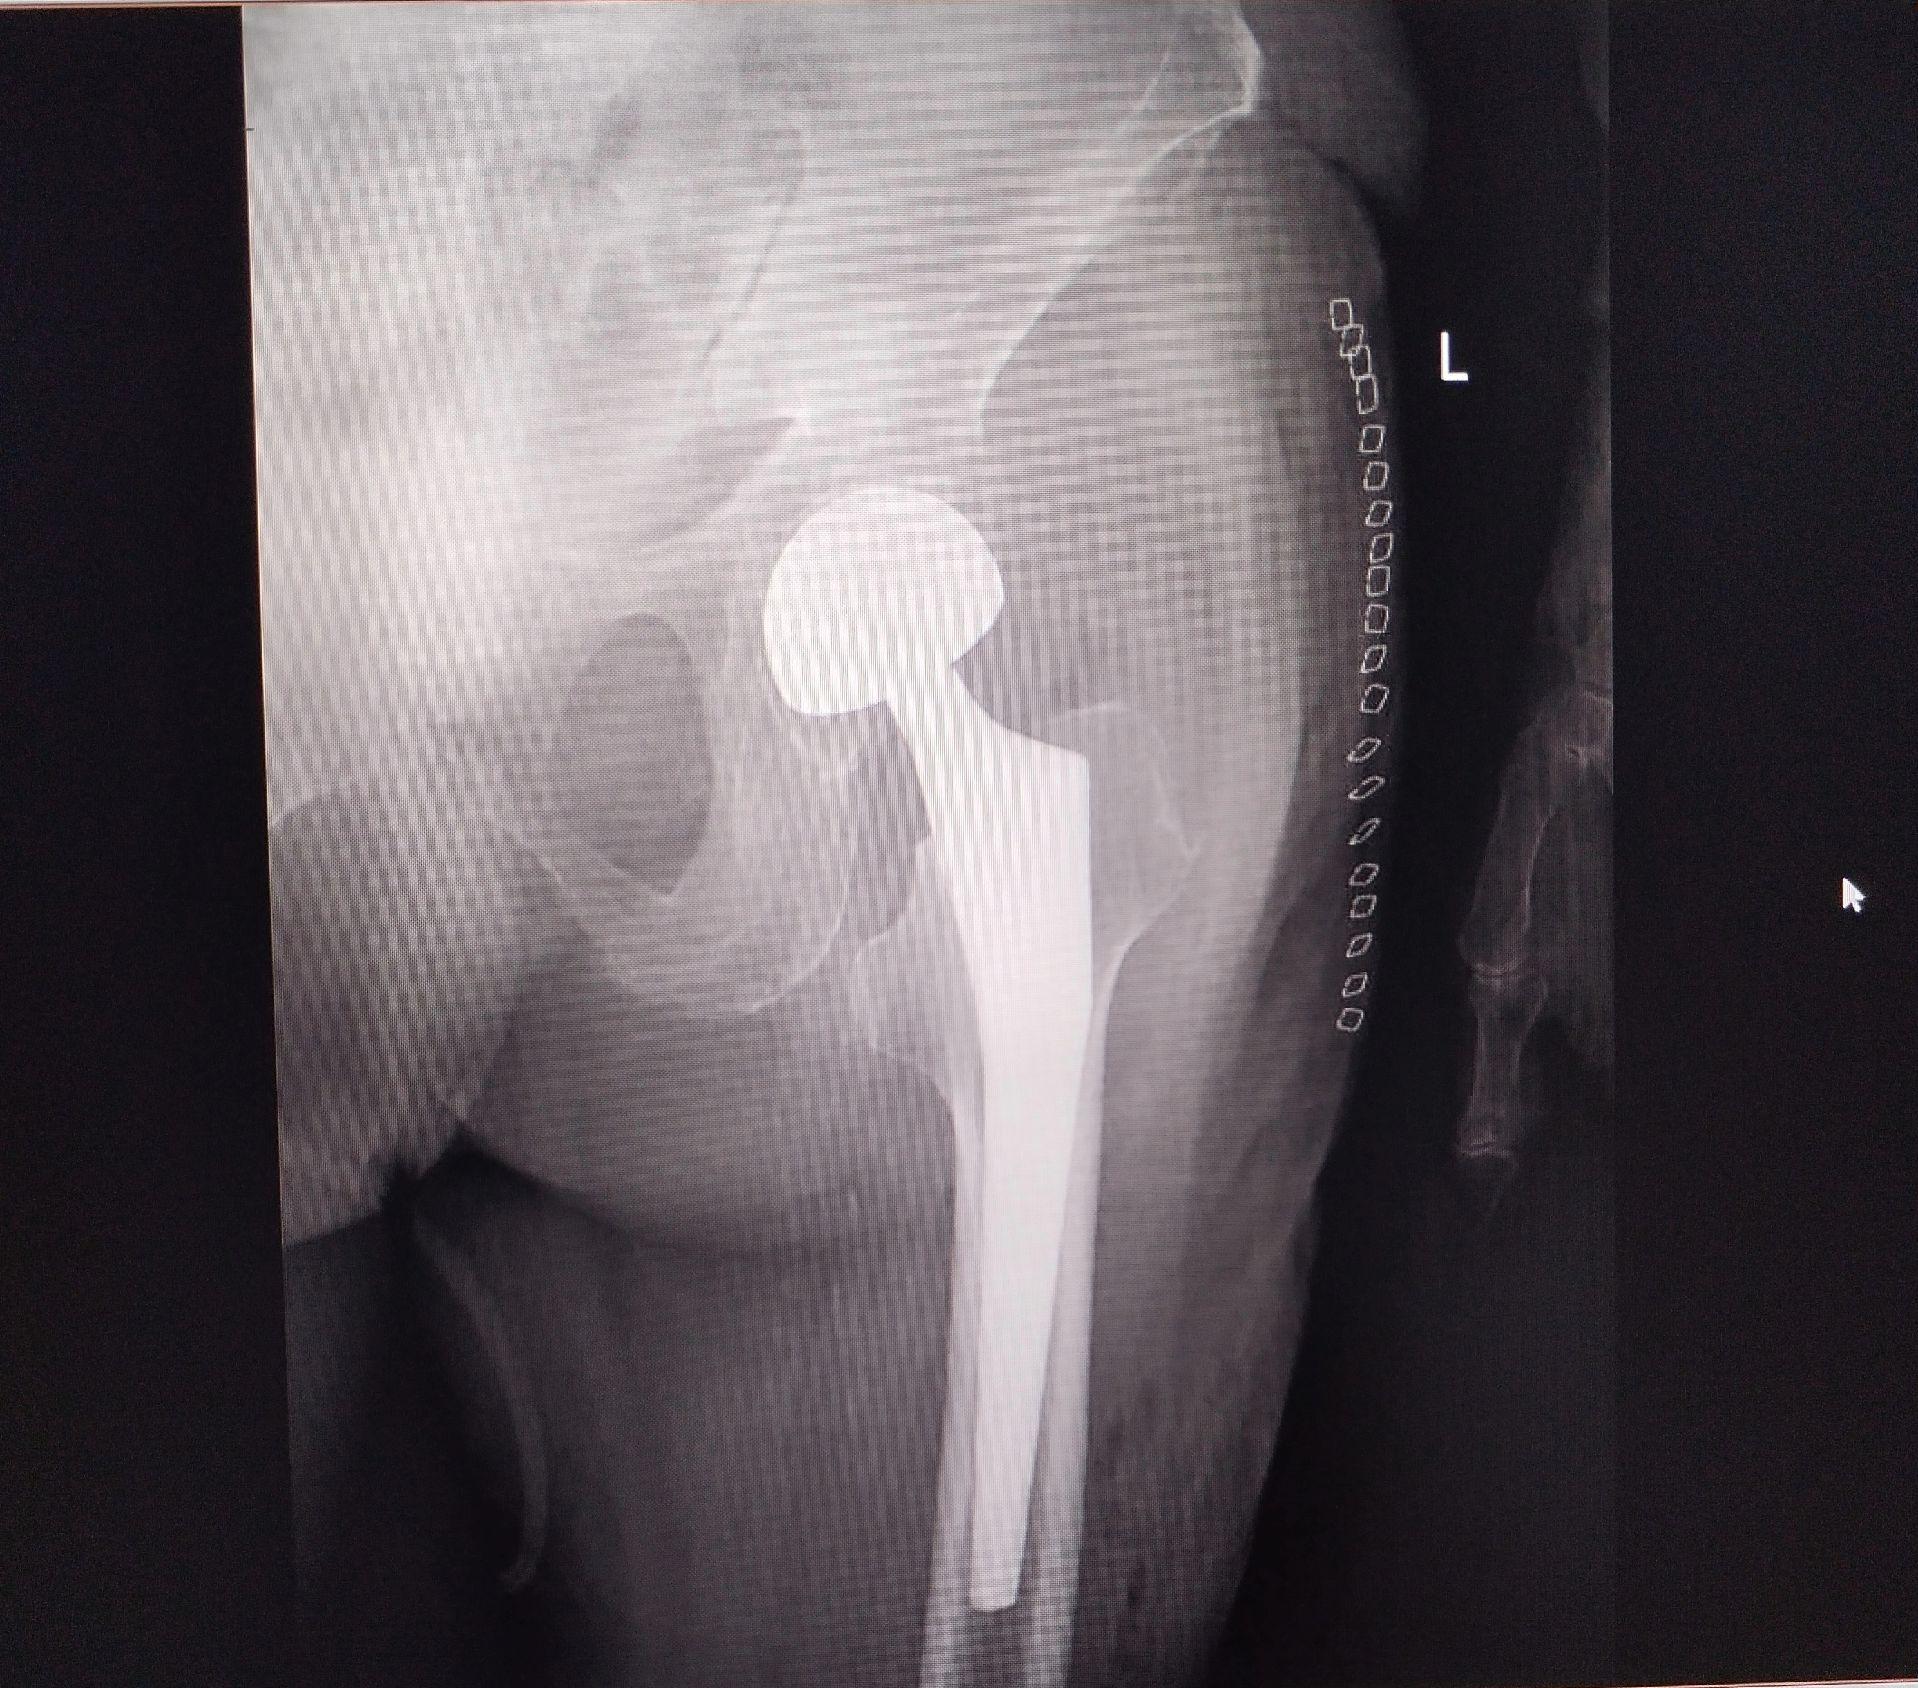

股骨颈骨折。101岁老太太,股骨颈骨折,鬼门关走一遭又回来了。家属的充分理解和支持,相关科室的齐心协力,是手术成功的关键因素🌹髋关节置换

股骨颈骨折。101岁老太太,股骨颈骨折,鬼门关走一遭又回来了。家属的充分理解和支持,相关科室的齐心协力,是手术成功的关键因素🌹